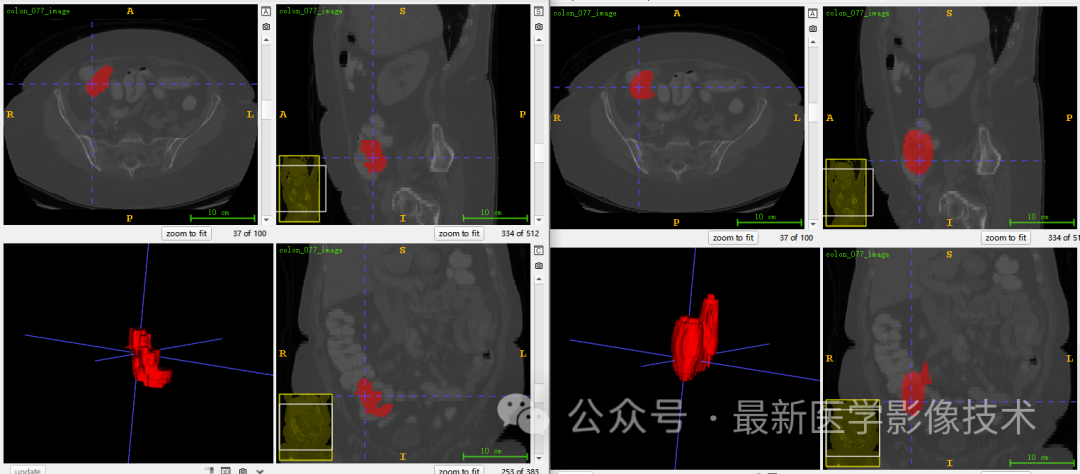

6、测试集分割结果